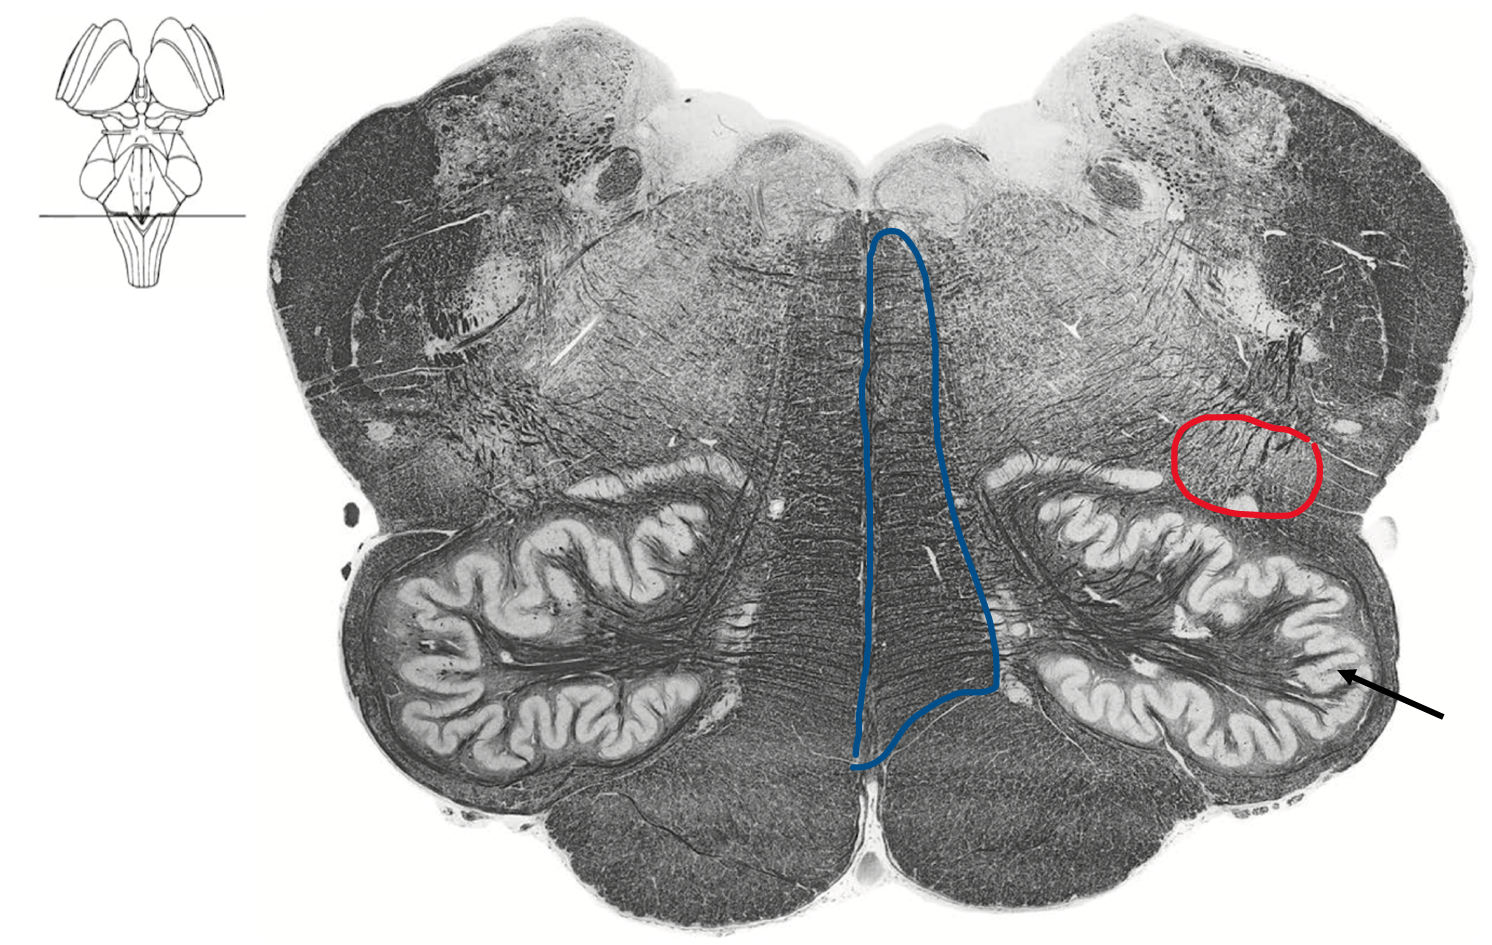

Caudal medulla

Somatic sensory decussation

Blue DCML where dorsal column becomes medial lemniscus

Red ALS spinothalamic tract

Caudel medulla at Obex (4th ventricle)

Blue medial lemniscus (DCML)